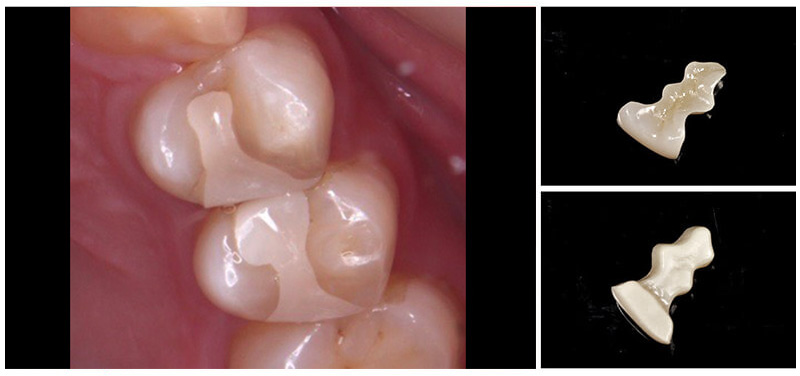

インレー

ジルコニアインレー・アンレー

セラミックインレー・アンレー

ゴールドインレー